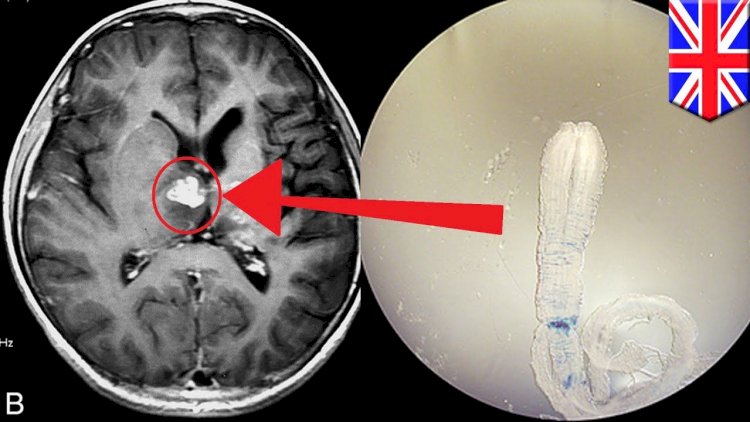

Əgər helmint qan axını ilə beyin və onurğa beyinə keçsə, ən ağır forması neyrosistiçerkoz yaranır.

Bu zaman beyinə təsir olur, kəskin baş ağrıları, qıcolmalar, huşun bulanması, yaddaş pozulması, diqqət yayğınlığı, nitqdə problemləry yaşanır.

Qan analizi, MRT, KT, beyində kist olduğu görüldükdə kistin çıxarılması zamanı cərrahlar kistin parazit yığnağı olduğunu görür.